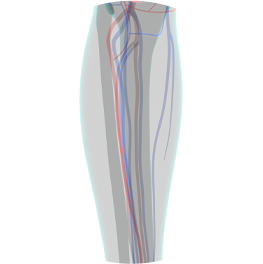

ハピスの超音波ふくらはぎ形成術は、高解像度医療用超音波機器を用いて、施術前・中・後の全過程をリアルタイムで確認します

これは単なる参考用撮影ではなく、

神経の位置

神経の深さ

筋肉の厚さ

血管分布

筋膜構造

をリアルタイム映像で確認しながら行う精密施術です。

従来法が解剖学的平均位置や電気刺激反応に依存していたのに対し、

ハピスは個々の実際の構造を直接確認しながら行う画像誘導施術(Ultrasound-guided procedure)です。